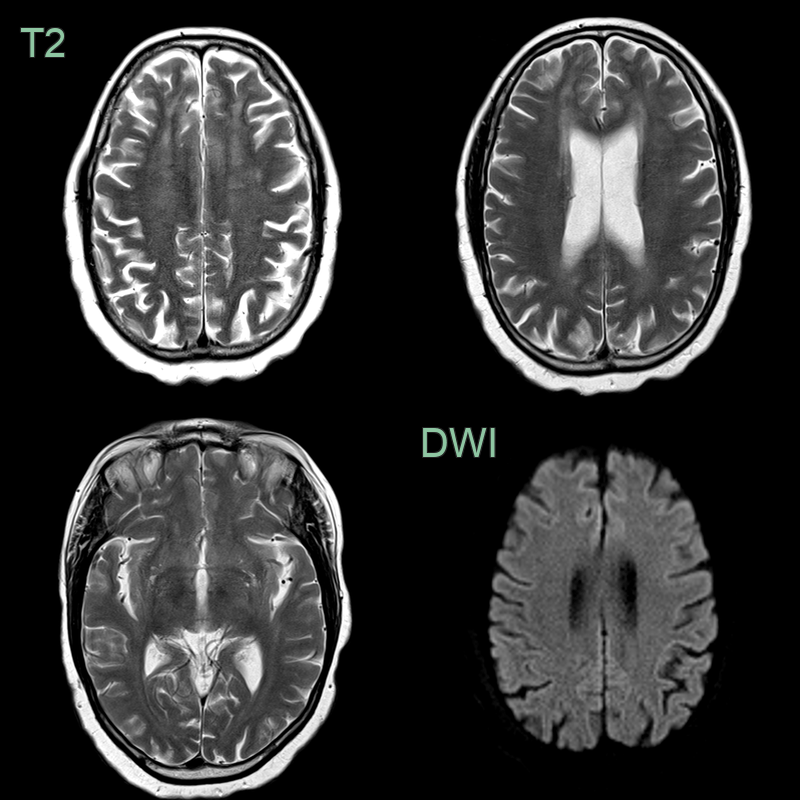

- A 50-year-old patient presented with cognitive impairment.

- A new diagnosis of HIV was made on admission.

- MRI showed patchy diffse white matter hyperintensity without enhancement in both cerebral hemispheres that spared the subcortical U fibres (red arrows).

- Following CSF analysis to exclude other causes and a follow-up scan 1 month later that showed no changes, the findings were ascribed to HIV encephalopathy.